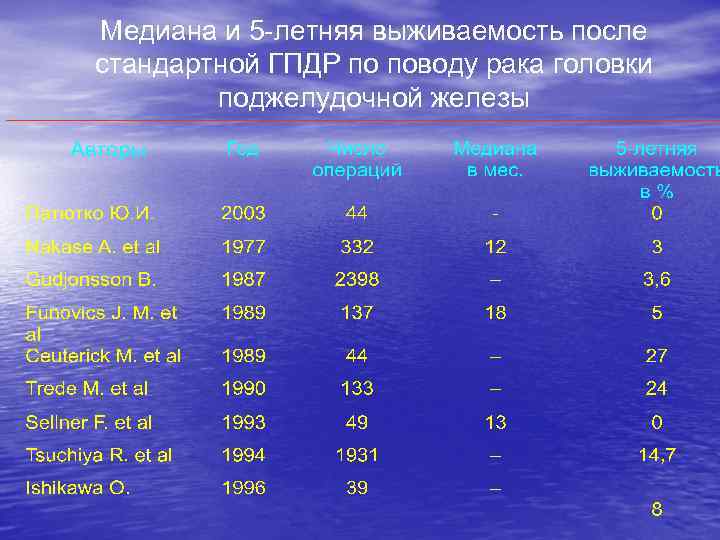

Медиана и 5 -летняя выживаемость после стандартной ГПДР по поводу рака головки поджелудочной железы